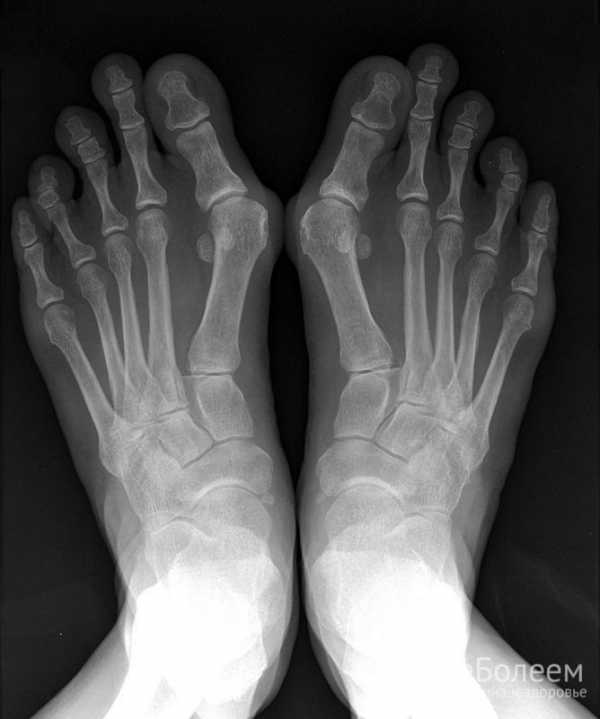

ΠΠ¦Π -ΠΈΡΡΠ»Π΅Π΄ΠΎΠ²Π°Π½ΠΈΠ΅ Π±ΠΈΠΎΠ»ΠΎΠ³ΠΈΡΠ΅ΡΠΊΠΎΠ³ΠΎ ΠΌΠ°ΡΠ΅ΡΠΈΠ°Π»Π° (ΠΊΡΠΎΠ²ΠΈ, ΠΌΠ°Π·ΠΊΠ° ΠΈΠ· ΠΏΠΎΠ»ΠΎΠ²ΡΡ ΠΏΡΡΠ΅ΠΉ, ΠΊΠ°Π»Π°) ΠΏΠΎΠ·Π²ΠΎΠ»ΡΠ΅Ρ ΠΏΡΠ΅Π΄ΠΏΠΎΠ»ΠΎΠΆΠΈΡΡ Π²Π΅ΡΠΎΡΡΠ½ΠΎΠ³ΠΎ Π²ΠΎΠ·Π±ΡΠ΄ΠΈΡΠ΅Π»Ρ ΠΈΠ½ΡΠ΅ΠΊΡΠΈΠΈ ΠΈ ΠΏΡΠΈΡΠΈΠ½Ρ ΡΠ΅Π°ΠΊΡΠΈΠ²Π½ΠΎΠ³ΠΎ Π°ΡΡΡΠΈΡΠ°. ΠΡΠΈ ΡΡΠΎΠΌ Π² ΠΏΠΎΡΠ΅Π²Π΅ ΡΡΡΡΠ°Π²Π½ΠΎΠΉ ΠΆΠΈΠ΄ΠΊΠΎΡΡΠΈ Π²ΠΎΠ·Π±ΡΠ΄ΠΈΡΠ΅Π»ΠΈ ΠΎΡΡΡΡΡΡΠ²ΡΡΡ, ΡΡΠΎ ΠΏΠΎΠ·Π²ΠΎΠ»ΡΠ΅Ρ Π΄ΠΈΡΡΠ΅ΡΠ΅Π½ΡΠΈΡΠΎΠ²Π°ΡΡ Π΄ΠΈΠ°Π³Π½ΠΎΠ· Ρ Π±Π°ΠΊΡΠ΅ΡΠΈΠ°Π»ΡΠ½ΡΠΌ Π°ΡΡΡΠΈΡΠΎΠΌ. ΠΡΠΈ ΡΠ΅Π°ΠΊΡΠΈΠ²Π½ΠΎΠΌ Π°ΡΡΡΠΈΡΠ΅ ΡΠ΅Π½ΡΠ³Π΅Π½ΠΎΠ³ΡΠ°ΡΠΈΡ ΡΡΡΡΠ°Π²ΠΎΠ² Π½Π΅ ΠΈΠΌΠ΅Π΅Ρ ΡΠ΅ΡΠ°ΡΡΠ΅Π³ΠΎ Π΄ΠΈΠ°Π³Π½ΠΎΡΡΠΈΡΠ΅ΡΠΊΠΎΠ³ΠΎ Π·Π½Π°ΡΠ΅Π½ΠΈΡ, ΠΎΠ΄Π½Π°ΠΊΠΎ Π½Π΅ΡΠ΅Π΄ΠΊΠΎ Π²ΡΡΠ²Π»ΡΠ΅Ρ Π½Π°Π»ΠΈΡΠΈΠ΅ ΠΏΡΡΠΎΡΠ½ΡΡ ΡΠΏΠΎΡ, ΠΏΠ°ΡΠ°Π²Π΅ΡΡΠ΅Π±ΡΠ°Π»ΡΠ½ΠΎΠΉ ΠΎΡΡΠΈΡΠΈΠΊΠ°ΡΠΈΠΈ, ΠΏΠ΅ΡΠΈΠΎΡΡΠΈΡΠ° ΠΊΠΎΡΡΠ΅ΠΉ ΡΡΠΎΠΏ. ΠΡΠΎΠ²Π΅Π΄Π΅Π½ΠΈΠ΅ ΠΏΡΠ½ΠΊΡΠΈΠΈ ΡΡΡΡΠ°Π²Π° ΠΈΠ»ΠΈ Π°ΡΡΡΠΎΡΠΊΠΎΠΏΠΈΠΈ ΠΎΠ±ΡΡΠ½ΠΎ Π½Π΅ ΡΡΠ΅Π±ΡΠ΅ΡΡΡ.

Π‘ ΠΏΠΎΠΌΠΎΡΡΡ ΡΠ΅Π½ΡΠ³Π΅Π½ΠΎΠ³ΡΠ°ΡΠΈΠΈ ΠΌΠΎΠΆΠ½ΠΎ Π²ΡΡΠ²ΠΈΡΡ ΠΏΡΠΈΠ·Π½Π°ΠΊΠΈ ΠΏΠΎΡΠ°ΠΆΠ΅Π½ΠΈΡ ΡΡΡΡΠ°Π²ΠΎΠ² β ΡΡΠΆΠ΅Π½ΠΈΠ΅ ΡΡΡΡΠ°Π²Π½ΠΎΠΉ ΡΠ΅Π»ΠΈ, ΡΡΠΎΠ·ΠΈΠΈ ΠΊΠΎΡΡΠ½ΡΡ ΠΏΠΎΠ²Π΅ΡΡ Π½ΠΎΡΡΠ΅ΠΉ. ΠΠ° Π²ΡΠΏΠΎΠ»Π½Π΅Π½Π½ΡΡ Π² Π΄Π²ΡΡ ΠΏΡΠΎΠ΅ΠΊΡΠΈΡΡ ΡΠ½ΠΈΠΌΠΊΠ°Ρ Π²ΠΈΠ·ΡΠ°Π»ΠΈΠ·ΠΈΡΡΡΡΡΡ ΠΏΡΡΠΎΡΠ½ΡΠ΅ ΡΠΏΠΎΡΡ, ΠΏΠ°ΡΠ°Π²Π΅ΡΡΠ΅Π±ΡΠ°Π»ΡΠ½Π°Ρ ΠΎΡΡΠΈΡΠΈΠΊΠ°ΡΠΈΡ, ΠΏΠ΅ΡΠΈΠΎΡΡΠΈΡ ΠΊΠΎΡΡΠ΅ΠΉ ΡΡΠΎΠΏ. Π Π±ΠΎΠ»ΡΡΠΈΠ½ΡΡΠ²Π΅ ΡΠ»ΡΡΠ°Π΅Π² Π½Π΅ ΡΡΠ΅Π±ΡΠ΅ΡΡΡ ΠΏΡΠΎΠ²Π΅Π΄Π΅Π½ΠΈΠ΅ Π°ΡΡΡΠΎΡΠΊΠΎΠΏΠΈΠΈ.

ΠΠ»ΠΈ ΠΏΠΎΡΠ°ΠΆΠ΅Π½ΠΈΡ ΡΡΡΡΠ°Π²ΠΎΠ² Ρ Π°ΡΠ°ΠΊΡΠ΅ΡΠ½Ρ ΠΎΡΡΡΠΎΠ΅ ΡΠ΅ΡΠ΅Π½ΠΈΠ΅ ΠΈ ΠΎΠ³ΡΠ°Π½ΠΈΡΠ΅Π½Π½ΠΎΠ΅ ΡΠΈΡΠ»ΠΎ ΠΏΠΎΡΠ°ΠΆΠ΅Π½Π½ΡΡ ΡΡΡΡΠ°Π²ΠΎΠ². Π£ 85% Π±ΠΎΠ»ΡΠ½ΡΡ Π½Π°Π±Π»ΡΠ΄Π°ΡΡ ΠΌΠΎΠ½ΠΎ- ΠΈ ΠΎΠ»ΠΈΠ³ΠΎΠ°ΡΡΡΠΈΡ. Π’ΠΈΠΏΠΈΡΠ½ΡΠΌ ΡΡΠΈΡΠ°ΡΡ Π°ΡΠΈΠΌΠΌΠ΅ΡΡΠΈΡΠ½ΡΠΉ Ρ Π°ΡΠ°ΠΊΡΠ΅Ρ ΠΏΠΎΡΠ°ΠΆΠ΅Π½ΠΈΡ ΡΡΡΡΠ°Π²ΠΎΠ². ΠΠΎ Π²ΡΠ΅Ρ ΡΠ»ΡΡΠ°ΡΡ Π½Π°Π±Π»ΡΠ΄Π°ΡΡ ΠΏΠΎΡΠ°ΠΆΠ΅Π½ΠΈΠ΅ ΡΡΡΡΠ°Π²ΠΎΠ² Π½ΠΈΠΆΠ½ΠΈΡ ΠΊΠΎΠ½Π΅ΡΠ½ΠΎΡΡΠ΅ΠΉ, Π·Π° ΠΈΡΠΊΠ»ΡΡΠ΅Π½ΠΈΠ΅ΠΌ ΡΠ°Π·ΠΎΠ±Π΅Π΄ΡΠ΅Π½Π½ΡΡ ΡΡΡΡΠ°Π²ΠΎΠ². Π ΡΠ°ΠΌΠΎΠΌ Π½Π°ΡΠ°Π»Π΅ Π·Π°Π±ΠΎΠ»Π΅Π²Π°Π½ΠΈΡ ΡΠ°Π·Π²ΠΈΠ²Π°Π΅ΡΡΡ Π²ΠΎΡΠΏΠ°Π»Π΅Π½ΠΈΠ΅ ΠΊΠΎΠ»Π΅Π½Π½ΡΡ , Π³ΠΎΠ»Π΅Π½ΠΎΡΡΠΎΠΏΠ½ΡΡ ΠΈ ΠΏΠ»ΡΡΠ½ΠΎΡΠ°Π»Π°Π½Π³ΠΎΠ²ΡΡ ΡΡΡΡΠ°Π²ΠΎΠ². ΠΠΎΠ·ΠΆΠ΅ ΠΌΠΎΠΆΠ΅Ρ ΡΠ°Π·Π²ΠΈΠ²Π°ΡΡΡΡ ΠΏΠΎΡΠ°ΠΆΠ΅Π½ΠΈΠ΅ ΡΡΡΡΠ°Π²ΠΎΠ² Π²Π΅ΡΡ Π½ΠΈΡ ΠΊΠΎΠ½Π΅ΡΠ½ΠΎΡΡΠ΅ΠΉ ΠΈ ΠΏΠΎΠ·Π²ΠΎΠ½ΠΎΡΠ½ΠΈΠΊΠ°. ΠΠ·Π»ΡΠ±Π»Π΅Π½Π½ΠΎΠΉ Π»ΠΎΠΊΠ°Π»ΠΈΠ·Π°ΡΠΈΠ΅ΠΉ ΠΏΠ°ΡΠΎΠ»ΠΎΠ³ΠΈΡΠ΅ΡΠΊΠΎΠ³ΠΎ ΠΏΡΠΎΡΠ΅ΡΡΠ° ΡΡΠΈΡΠ°ΡΡ ΠΏΠ»ΡΡΠ½Π΅ΡΠ°Π»Π°Π½Π³ΠΎΠ²ΡΠ΅ ΡΡΡΡΠ°Π²Ρ Π±ΠΎΠ»ΡΡΠΈΡ ΠΏΠ°Π»ΡΡΠ΅Π² ΡΡΠΎΠΏ, ΡΡΠΎ Π½Π°Π±Π»ΡΠ΄Π°ΡΡ Π² ΠΏΠΎΠ»ΠΎΠ²ΠΈΠ½Π΅ ΡΠ»ΡΡΠ°Π΅Π². Π Π΅ΠΆΠ΅ Π²ΡΡΠ²Π»ΡΡΡ ΠΏΠΎΡΠ°ΠΆΠ΅Π½ΠΈΠ΅ Π΄ΡΡΠ³ΠΈΡ ΠΏΠ»ΡΡΠ½Π΅ΡΠ°Π»Π°Π½Π³ΠΎΠ²ΡΡ ΡΡΡΡΠ°Π²ΠΎΠ² ΠΈ ΠΌΠ΅ΠΆΡΠ°Π»Π°Π½Π³ΠΎΠ²ΡΡ ΡΡΡΡΠ°Π²ΠΎΠ² ΠΏΠ°Π»ΡΡΠ΅Π² ΡΡΠΎΠΏ, ΡΡΡΡΠ°Π²ΠΎΠ² ΠΏΡΠ΅Π΄ΠΏΠ»ΡΡΠ½Ρ, Π³ΠΎΠ»Π΅Π½ΠΎΡΡΠΎΠΏΠ½ΡΡ ΠΈ ΠΊΠΎΠ»Π΅Π½Π½ΡΡ ΡΡΡΡΠ°Π²ΠΎΠ². ΠΡΠΈ ΡΡΠΎΠΌ Π·Π°Π±ΠΎΠ»Π΅Π²Π°Π½ΠΈΠΈ Π½Π΅ΡΠ΅Π΄ΠΊΠΎ ΡΠ°Π·Π²ΠΈΠ²Π°ΡΡΡΡ Π΄Π°ΠΊΡΠΈΠ»ΠΈΡΡ ΠΎΠ΄Π½ΠΎΠ³ΠΎ ΠΈΠ»ΠΈ Π½Π΅ΡΠΊΠΎΠ»ΡΠΊΠΈΡ ΠΏΠ°Π»ΡΡΠ΅Π² ΡΡΠΎΠΏ, ΡΠ°ΡΠ΅ Π²ΡΠ΅Π³ΠΎ ΠΏΠ΅ΡΠ²ΡΡ , Ρ ΡΠΎΡΠΌΠΈΡΠΎΠ²Π°Π½ΠΈΠ΅ΠΌ ΡΠΎΡΠΈΡΠΊΠΎΠΎΠ±ΡΠ°Π·Π½ΠΎΠΉ Π΄Π΅ΡΠΎΡΠΌΠ°ΡΠΈΠΈ, ΠΊΠΎΡΠΎΡΡΠ΅ ΡΠ²Π»ΡΡΡΡΡ ΡΠ΅Π·ΡΠ»ΡΡΠ°ΡΠΎΠΌ Π²ΠΎΡΠΏΠ°Π»ΠΈΡΠ΅Π»ΡΠ½ΡΡ ΠΈΠ·ΠΌΠ΅Π½Π΅Π½ΠΈΠΉ Π΅ ΠΏΠ΅ΡΠΈΠ°ΡΡΠΈΠΊΡΠ»ΡΡΠ½ΡΡ ΡΡΡΡΠΊΡΡΡΠ°Ρ ΠΈ ΠΏΠ΅ΡΠΈΠΎΡΡΠ°Π»ΡΠ½ΠΎΠΉ ΠΊΠΎΡΡΠΈ.

ΠΠ°ΠΈΠ½ΡΠ΅ΡΠ΅ΡΠΎΠ²Π°Π½Π½ΠΎΡΡΡ ΡΡΡΡΠ°Π²ΠΎΠ² ΠΏΡΠ΅Π΄ΠΏΠ»ΡΡΠ½Ρ ΠΈ Π²ΠΎΡΠΏΠ°Π»ΠΈΡΠ΅Π»ΡΠ½ΡΠΉ ΠΏΡΠΎΡΠ΅ΡΡ Π² ΡΠ²ΡΠ·ΠΎΡΠ½ΠΎΠΌ Π°ΠΏΠΏΠ°ΡΠ°ΡΠ΅ ΡΡΠΎΠΏ Π±ΡΡΡΡΠΎ ΠΏΡΠΈΠ²ΠΎΠ΄ΡΡ ΠΊ ΡΠ°Π·Π²ΠΈΡΠΈΡ Π²ΡΡΠ°ΠΆΠ΅Π½Π½ΠΎΠ³ΠΎ ΠΏΠ»ΠΎΡΠΊΠΎΡΡΠΎΠΏΠΈΡ (Β«Π³ΠΎΠ½ΠΎΡΠ΅ΠΉΠ½Π°Ρ ΡΡΠΎΠΏΠ°Β»). ΠΠ½Π°ΡΠΈΡΠ΅Π»ΡΠ½ΠΎ ΡΠ΅ΠΆΠ΅ Π½Π°Π±Π»ΡΠ΄Π°ΡΡ Π»ΠΎΠΊΠ°Π»ΠΈΠ·Π°ΡΠΈΡ Π²ΠΎΡΠΏΠ°Π»ΠΈΡΠ΅Π»ΡΠ½ΠΎΠ³ΠΎ ΠΏΡΠΎΡΠ΅ΡΡΠ° Π² ΡΡΡΡΠ°Π²Π°Ρ Π²Π΅ΡΡ Π½ΠΈΡ ΠΊΠΎΠ½Π΅ΡΠ½ΠΎΡΡΠ΅ΠΉ Ρ Π·Π°ΠΈΠ½ΡΠ΅ΡΠ΅ΡΠΎΠ²Π°Π½Π½ΠΎΡΡΡΡ ΠΌΠ΅ΠΆΡΠ°Π»Π°Π½Π³ΠΎΠ²ΡΡ , ΠΏΡΡΡΠ½ΠΎ-ΡΠ°Π»Π°Π½Π³ΠΎΠ²ΡΡ ΠΈ Π»ΡΡΠ΅Π·Π°ΠΏΡΡΡΠ½ΡΡ ΡΡΡΡΠ°Π²ΠΎΠ². ΠΠ΄Π½Π°ΠΊΠΎ ΡΡΠΎΠΉΠΊΠΎΠ³ΠΎ ΠΏΡΠΎΡΠ΅ΡΡΠ° ΡΡΠΎΠΉ Π»ΠΎΠΊΠ°Π»ΠΈΠ·Π°ΡΠΈΠΈ ΠΈ ΡΠ΅ΠΌ Π±ΠΎΠ»Π΅Π΅ Π΄Π΅ΡΡΡΡΠΊΡΠΈΠΈ ΡΡΡΡΠ°Π²Π½ΡΡ ΠΏΠΎΠ²Π΅ΡΡ Π½ΠΎΡΡΠ΅ΠΉ Π½Π΅ Π½Π°Π±Π»ΡΠ΄Π°ΡΡ.